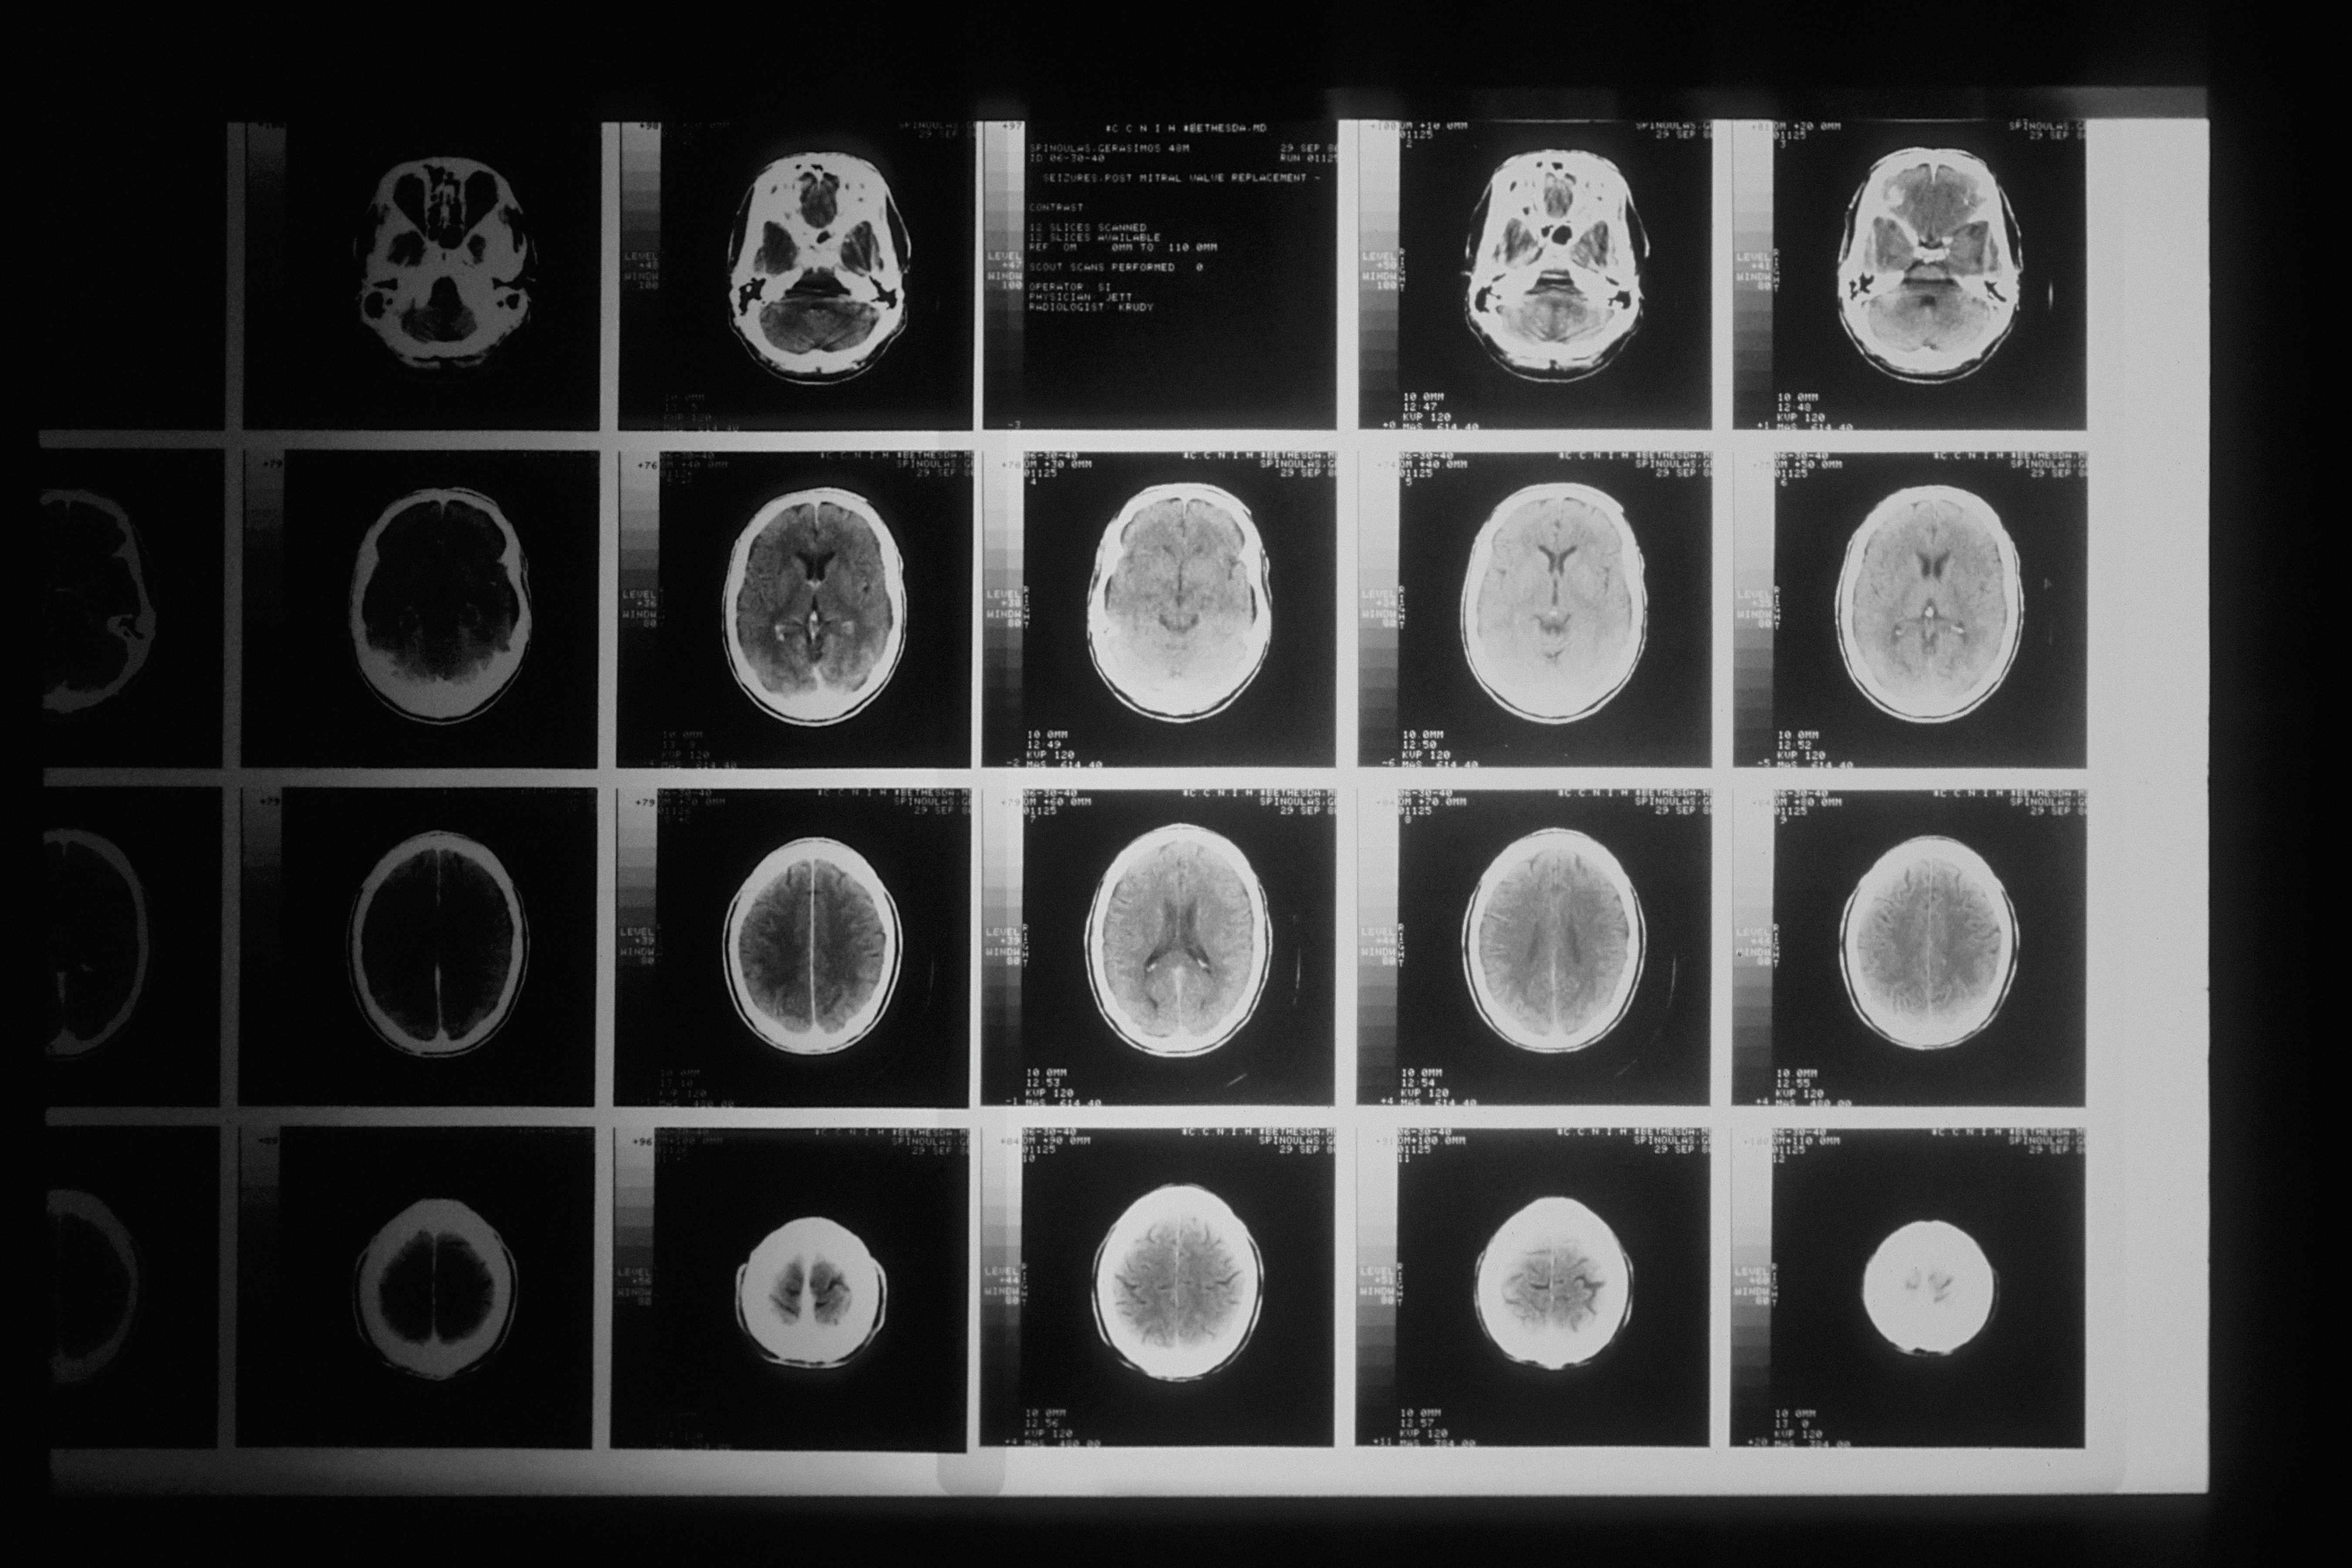

Prebacivanje između jezika, sprečavanje izgovora pogrešne riječi, pamćenje različitih rječnika i izbor pravog izraza stalno opterećuju ove sustave. Rad je pokazao da ljudi koji koriste dva jezika tijekom života obično imaju veći hipokampus.

To znači da je hipokampus, ključna moždana regija za formiranje sjećanja, fizički veći. Veći ili strukturno jači hipokampus općenito je povezan s boljim pamćenjem i većom otpornošću na smanjenje volumena mozga uslijed starenja ili neurodegenerativnih bolesti poput Alzheimerove.